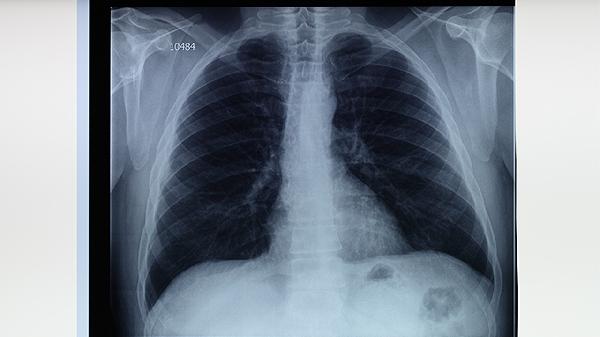

胸部X线检查可发现肺结核引起的肺部病变,如浸润影、空洞形成等。典型表现为上叶尖后段或下叶背段病变。该检查具有辐射量小、费用低的优点,是肺结核筛查的常规手段。但早期病变或某些特殊类型肺结核可能表现不典型。